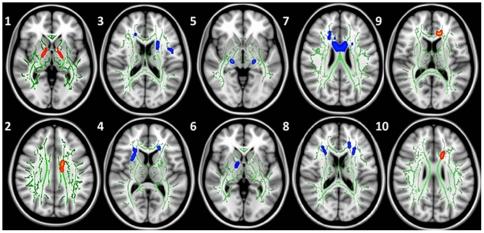

WE DERIVED FOUR FACTORS: Self, Social-Emotional, Financial-Intellectual, and Spirituality. While showing limited relationships to psychological and neuropsychological measures, both white matter integrity and gray matter density showed significant relationships with SWEET factors.

These findings suggest that while individual responses may not be indicative of psychological or cognitive processes they may relate to changes in brain structure. Several of these structures, such as the negative correlation of the affective impact of world with the dorsal anterior corpus callosum white matter integrity have been observed in psychiatric conditions (e.g., obsessive-compulsive disorder). Further longitudinal research using the SWEET may help understand the impact of dramatic shifts in self/world conceptualization and potentially link these shifts to underlying changes in brain structure.